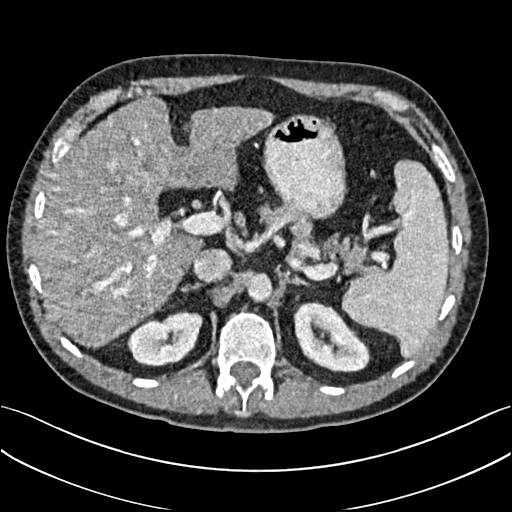

To demonstrate the effectiveness of the proposed network, we perform the qualitative comparisons over three representative abdominal images presented in Figs. 3, 5 and 7. For better evaluations of the image quality with different denoising models, zoomed regions-of-interest (ROIs) are marked by red rectangles and shown in Figs. 4, 6 and 8 respectively. Note that all results from different denoising models focus on two aspects: content restoration and noise-reduction. All CT images in axial view are displayed in the angiography window [-160, 240]HU.

The real NDCT images and corresponding LDCT images are presented in Figs. 3a and 3b. As observed, there are distinctions between ground truth (NDCT) images and LDCT images. Figs. 3a and 7a show the lesions/metastasis. Fig. 5a presents focal fatty sparing/focal fat. In Figs. 4a, 6a and 8a, these lesions can be clearly observed in NDCT images; in contrast, from Figs. 4b, 6b, and 8b, it can be seen that the original LDCT image is noisy, and lacks structural features for task-based clinical diagnosis. All adopted denoising models suppress noise to some extent.